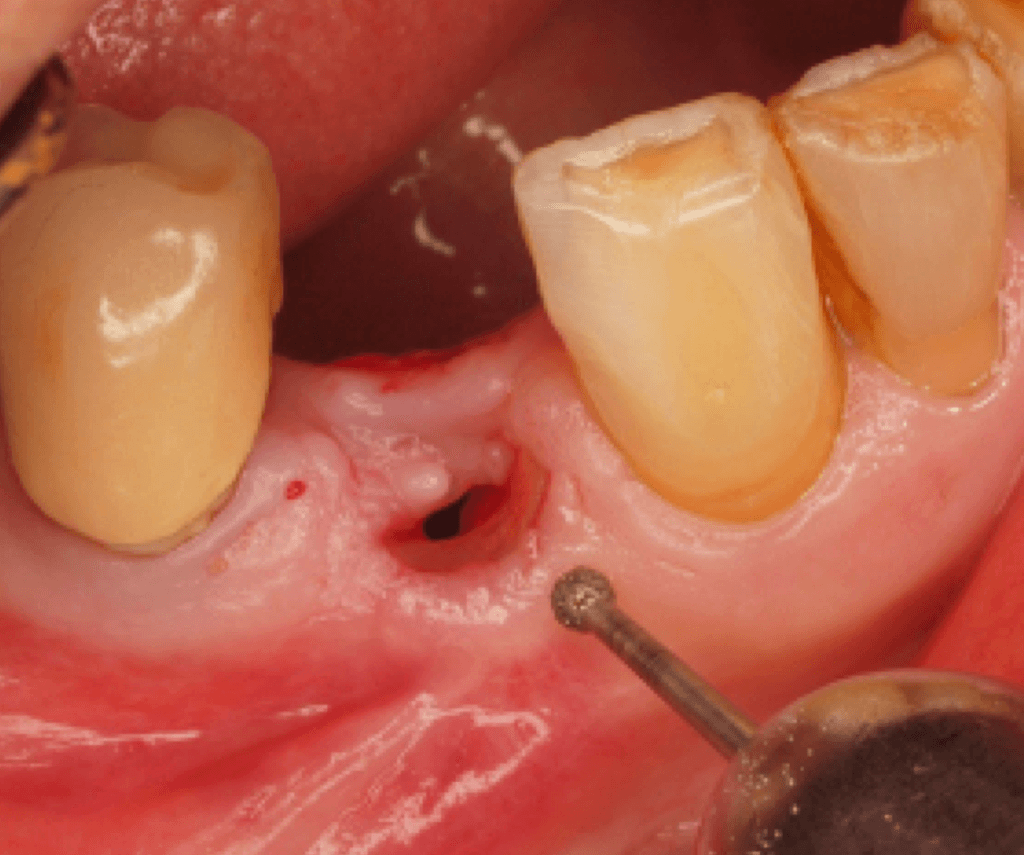

Inside Partial Extraction Therapy by CIDN

Learn how to Manage Complications

Assess various PET cases